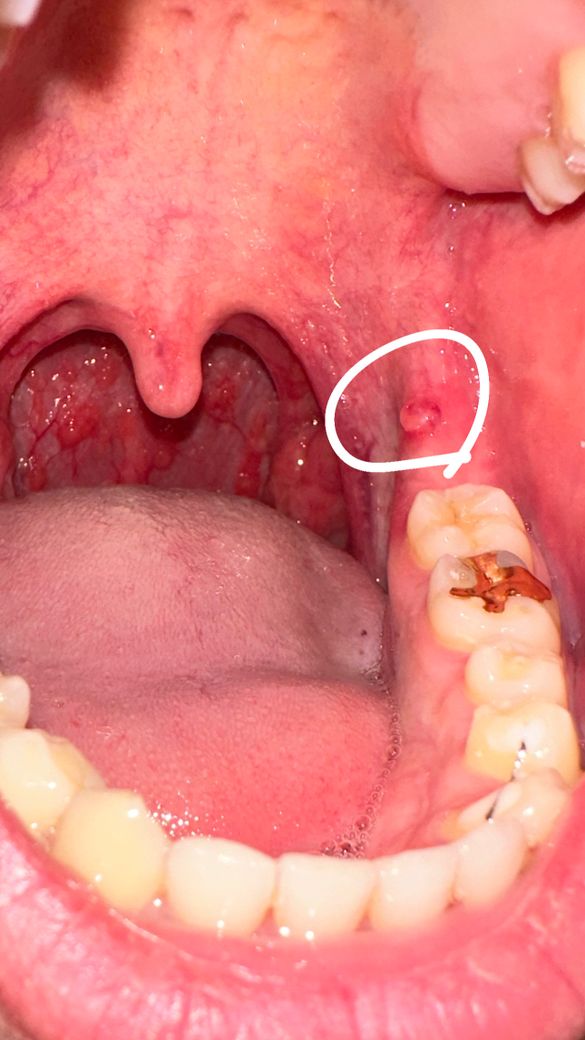

입 안 잇몸에 물집이 생겼습니다…..

며칠전부터 목이 감기증상처럼 아파서 계속 핸드폰으로 확인했는데 오늘보니 잇몸에 물집같은게 한 개 생겼습니다. 물집 자체는 혀로 만지면 불편하지 따로 아프진 않습니다. 생각해보면 이 부위에 오래전부터 저런것이 가끔 생겼습니다.

일주일전에 구강성교를 했었는데 상대방 성기에 뾰루지같은게 두개 있었는데 이것이랑 연관이 되있을까요? 혹시 헤르패스같은 성병인지, 그냥 피곤해서 생긴 증상인지 궁금합니다 (제가 요즘 잘때 선풍기를 얼굴 밑을 향하게 해서 자는데 이것도 연관이 있을수 있나요?) 이럴경우 이빈후과를 가야하나요? 감사합니다.